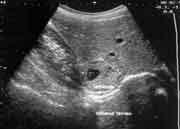

Размеры выявленных опухолей колебались от 2 до 10 см в диаметре. Все имели капсулу, гладкую поверхность, округлую или овальную форму. Небольшие опухоли имели однородную изоэхогенную структуру (Рис. 3), а в 4 случаях, когда размер опухоли превышал 4 см, внутренняя эхоструктура была представлена неравномерным чередованием участков повышенной и пониженной эхогенности за счет зон некроза, дегенеративных изменений и обызвествлений, что подтверждалось при гистологических исследованиях удаленных опухолей (Рис. 4, 5).

Рис. 4. Опухоль надпочечника с неоднородной структурой.

Увеличить

Рис. 5. Опухоль надпочечника с дегенерацией в центре.